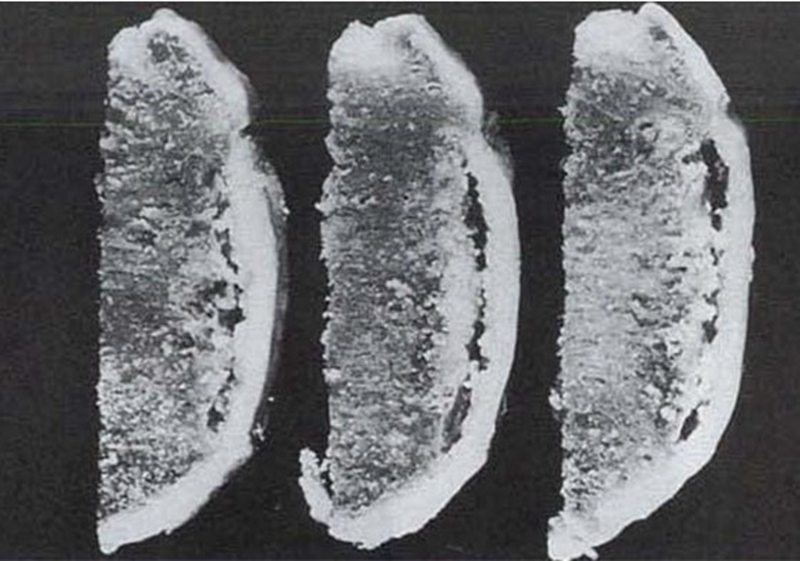

病理显示软骨下不完全骨折或局灶性软骨下骨坏死